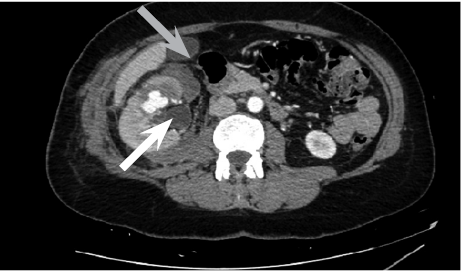

Cause of hematuria had to be determined, therefore urgent contrast enhanced computed tomography was performed (Figure 2) – contrast extravazation was found on the lower third of the right kidney (area of surgery), along with subcapsular hemathoma. Right hydroureteronephrosis and fluid in pelvis were observed. Blood clots and a small amount of contrast in the bladder were seen.

433238.png

Figure 2. Contrast extravazation was found on the lower third of the right kidney (white arrow), subcapsular hemathoma (grey arrow)